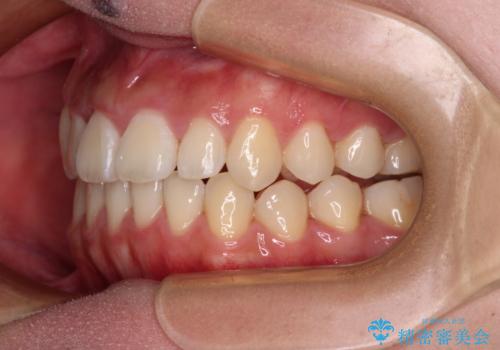

上顎骨を拡大することで、八重歯やデコボコを歯列に収めることができ、下顎の歯が外に位置していた奥歯の咬み合わせも改善することができました。

スペースも短期間に獲得できるため、1年程度で治療を終えることができました。